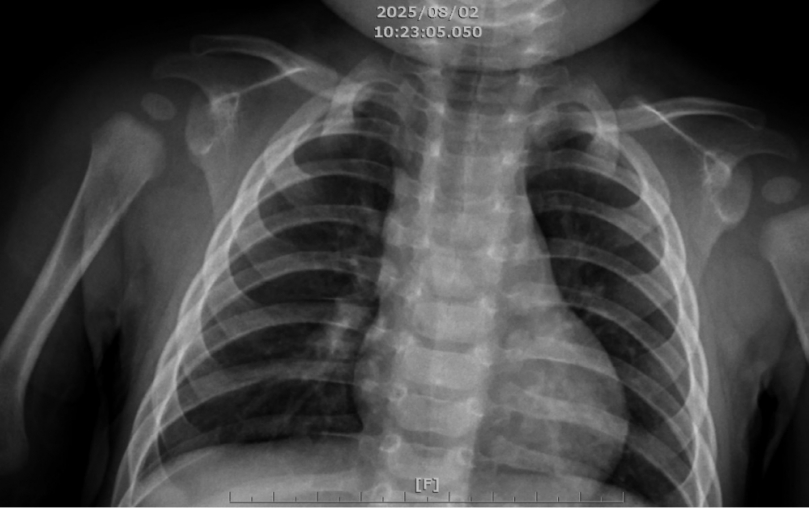

院方也不敢輕忽,針對症狀先排除黴漿菌感染,拍了胸部x光檢查,當時雙肺影像清澈,推論感染肺炎鏈球菌,擔心病菌兇猛又快速,收治住院治療。檢驗結果出來,男嬰果然感染病程快又猛、嚴重會併發肺炎、腦膜炎,致死率超過3成的「大魔王」血清型肺炎鏈球菌。